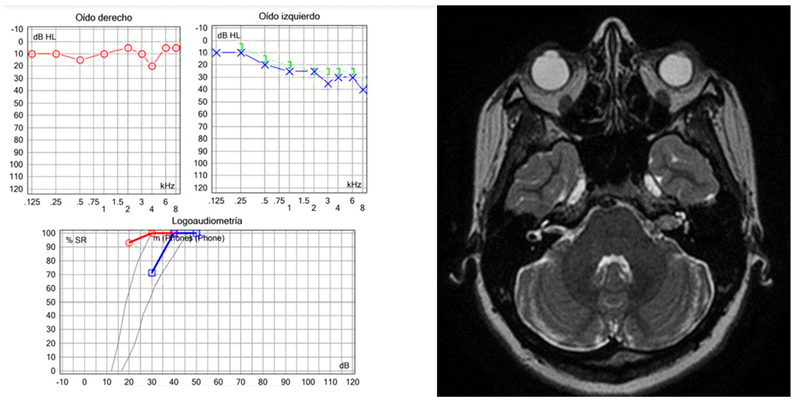

En las Figuras 3, 4, 5 y 6 se presentan algunos ejemplos de hipoacusia sensorineural asimétrica vistos comúnmente en la clínica y que ejemplifican la necesidad de realizar IRM.

Estos son ejemplos de casos clínicos que vemos con frecuencia en la consulta otoneurológica/neurotológica. La asimetría audiométrica aunque pueda deberse a una hipoacusia súbita o presbiacusia, siempre debe hacernos sospechar de una lesión retrococlear. La presencia de reflejos estapediales reclutados, su ausencia y el patrón de discriminación en la logoaudiometría pueden sugerir un origen coclear de la hipoacusia, pero no pueden por sí solos descartar una lesión retrococlear.